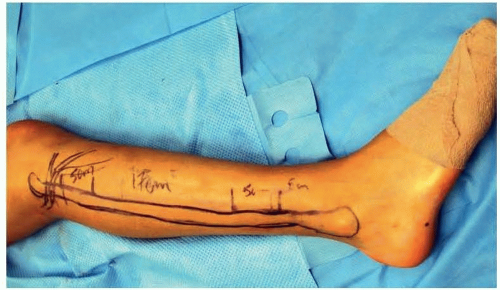

Prior to incision, anatomical landmarks including the head of the fibula, lateral malleolus, and anterior and posterior border of the fibula are marked. The posterior border of the fibula correlates with the posterior intermuscular septum encasing the vascular supply to the skin paddle (FIG 3).

FIG 3 • Intraoperative marking of anatomical landmarks for an ipsilateral fibula harvest in the lateral decubitus position: head of the fibula, lateral malleolus, and anteroposterior fibular border.